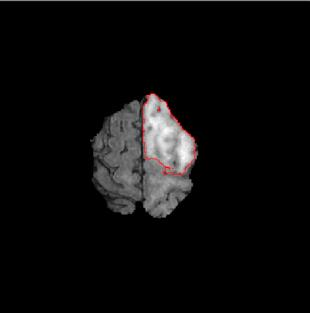

Machine learning has been widely adopted for medical image analysis in recent years given its promising performance in image segmentation and classification tasks. The success of machine learning, in particular supervised learning, depends on the availability of manually annotated datasets. For medical imaging applications, such annotated datasets are not easy to acquire, it takes a substantial amount of time and resource to curate an annotated medical image set. In this paper, we propose an efficient annotation framework for brain MR images that can suggest informative sample images for human experts to annotate. We evaluate the framework on two different brain image analysis tasks, namely brain tumour segmentation and whole brain segmentation. Experiments show that for brain tumour segmentation task on the BraTS 2019 dataset, training a segmentation model with only 7% suggestively annotated image samples can achieve a performance comparable to that of training on the full dataset. For whole brain segmentation on the MALC dataset, training with 42% suggestively annotated image samples can achieve a comparable performance to training on the full dataset. The proposed framework demonstrates a promising way to save manual annotation cost and improve data efficiency in medical imaging applications.

翻译:近年来,由于在图像分割和分类任务方面表现良好,医学图像分析广泛采用了机器学习。机器学习的成功,特别是监督学习的成功,取决于手动附加说明数据集的可用性。对于医疗成像应用来说,这种附加说明数据集不容易获得,需要大量的时间和资源来翻译附加说明的医学成像集。在本文件中,我们建议为大脑MR图像建立一个高效的注释框架,为人类专家提供信息性样图像,供人类专家作说明。我们评估了两种不同的大脑图像分析任务的框架,即脑肿瘤分割和整个大脑分割。实验显示,对于BRATS 2019数据集的脑肿瘤分割任务,培训一个只有7%的附加说明图像样本的分解模型,其性能与全数据集培训的性能相当。对于MALC数据集的整个大脑分割,用42%的附加说明性图像样本进行的培训,可以实现与全数据集培训的类似性能。拟议的框架展示了节省人工注解成本和提高医疗成像应用数据效率的有希望的方法。